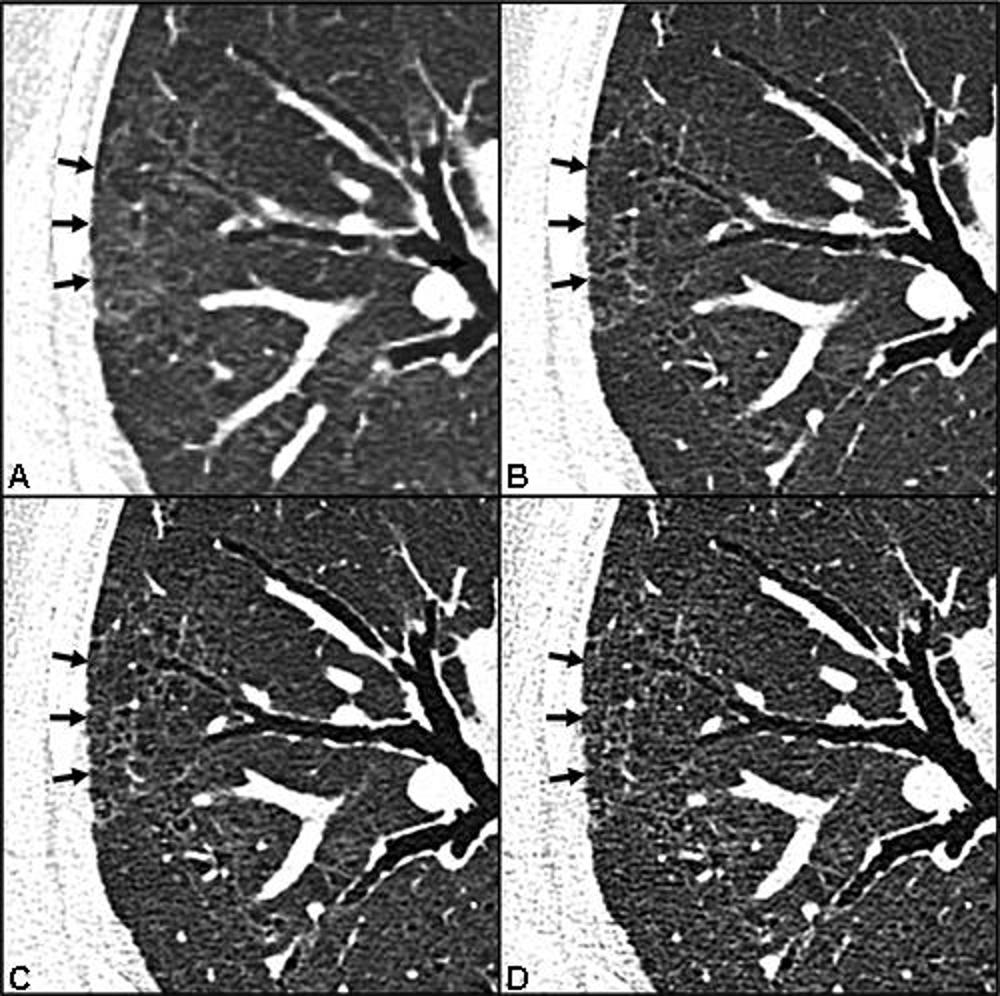

Figure 4. Comparison of image quality between energy-integrating detector and photon-counting detector CT images: Axial CT lung images without contrast agent of a 66-year-old man with persistent exertional dyspnea, chronic fatigue and anosmia 94 days after COVID-19: Subjective image quality was rated as ‘definitely better with likely effect on detectability of lung abnormalities’ for 1.0mm photon-counting detector (PCD) CT (B) compared with 1.0mm energy-integrating detector (EID) CT (A) images, ‘definitely better with unclear effect on detectability of lung abnormalities’ for 0.4mm (C) compared with 1.0mm (B) PCD CT images, and ‘similar without decrement or benefit’ for 0.2mm (D) compared with 0.4mm (C) PCD CT images.

High-res (TIF) version